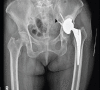

Case report: We present this challenging and unique case of a 64-year-old female patient where the acetabular component screw was found to be adherent to the external iliac vessels, with vascular injury imminent. During revision surgery, the iliac vessels were first released free of all adhesions with the intrapelvis screw using an ilioinguinal incision and retroperitoneal approach. The prosthesis was removed using a posterior approach to the hip joint. Definitive surgery was performed after 2 weeks.